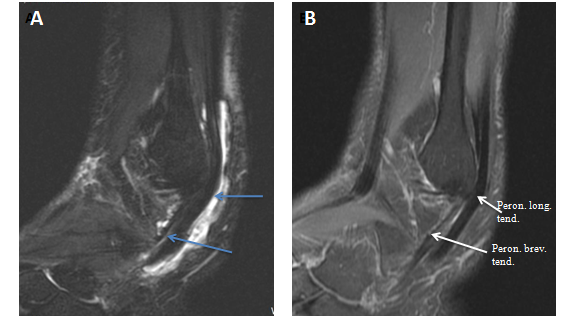

Coronal fat saturated proton density MRI image of the right ankle showed both peroneal tendons located above the peroneal tubercle, they were surrounded with soft tissue swelling and high T2 signal intensity which indicates fluid effusion. Abnormal signal intensity was also seen within both peroneal tendons indicating tendonitis. The left ankle showed a prominent peroneal tubercle. Peroneal tendons were normal and intact (Figure 4).

Figure 4 (A) Coronal fat saturated proton density MRI image of the right ankle shows the hypertrophic peroneal tubercle (red arrow). Both peroneal tendons are located above the tubercle, they are surrounded with soft tissue swelling and high T2 signal intensity (blue short arrow). Abnormal signal intensity is also seen within both peroneal tendons. (B) Left ankle for comparison shows a prominent peroneal tubercle but normal peroneal tendons.

Sagittal fat saturated proton density MRI image of the right ankle displayed a significant amount of fluid extending down along both peroneal tendons till their bone attachments (Figure 6).

Figure 6 (A) Sagittal fat saturated proton density MRI image of the right ankle shows fluid in the common peroneal sheath and around the peroneus longus and breves tendons (blue arrows). (B) Left ankle for comparison shows no fluid around the tendons.